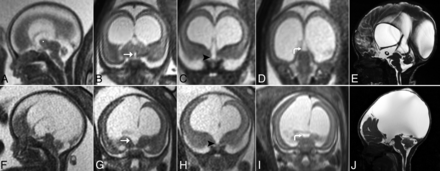

Fetal MRI of a 22-weeks’-gestation male fetus with aqueductal stenosis (A, B, C, and D). A, Sagittal T2WI shows a thick TMI (star) and aqueductal stenosis with hydrocephalus. Coronal T2WI shows a small central third ventricle diameter (white arrow, B) but an enlarged supraoptic recess (black arrowhead, C) and a large supraspinal recess (curved white arrow, D). Postnatal 1-day-old sagittal T2WI (E) of the same patient confirms thickening of the TMI (star) and CAS, with milder central third ventricle dilation. Fetal MRI of a 21-weeks’-gestation female fetus with aqueductal stenosis (F, G, H, and I). F, Sagittal T2WI shows aqueductal stenosis and marked dilation of the third ventricle with no visible TMI. Coronal T2WI shows an enlarged central third ventricle (white arrow, G), an enlarged supraoptic recess (black arrowhead on H), and an enlarged suprapineal recess (curved white arrow, I). Postnatal 2-day-old sagittal T2WI (J) of the same patient confirms CAS with massive supratentorial ventriculomegaly and hydrocephalus.